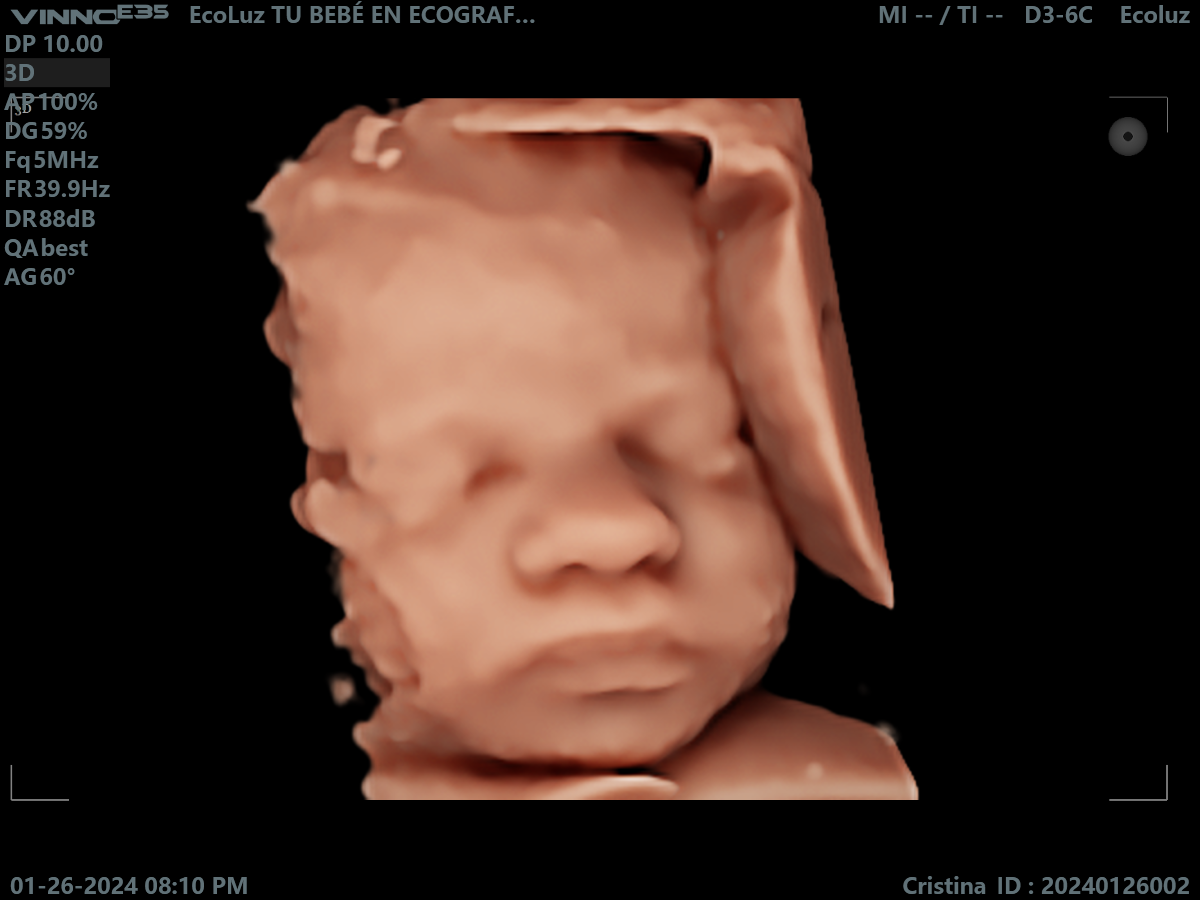

En esta etapa del embarazo, la eco 30 semanas muestra un bebé más grande y con menos espacio para moverse, lo que facilita ver su rostro más fijo en pantalla.…

Muchas familias consideran la ecografía de 30 semanas como una de las más impactantes visualmente. La definición del rostro y los detalles son sorprendentes. 💫 En EcoLuz 5D creamos un…

A las 30 semanas, el bebé ya tiene una expresión muy reconocible. La ecografía 30 semanas permite captar gestos únicos que emocionan a toda la familia.